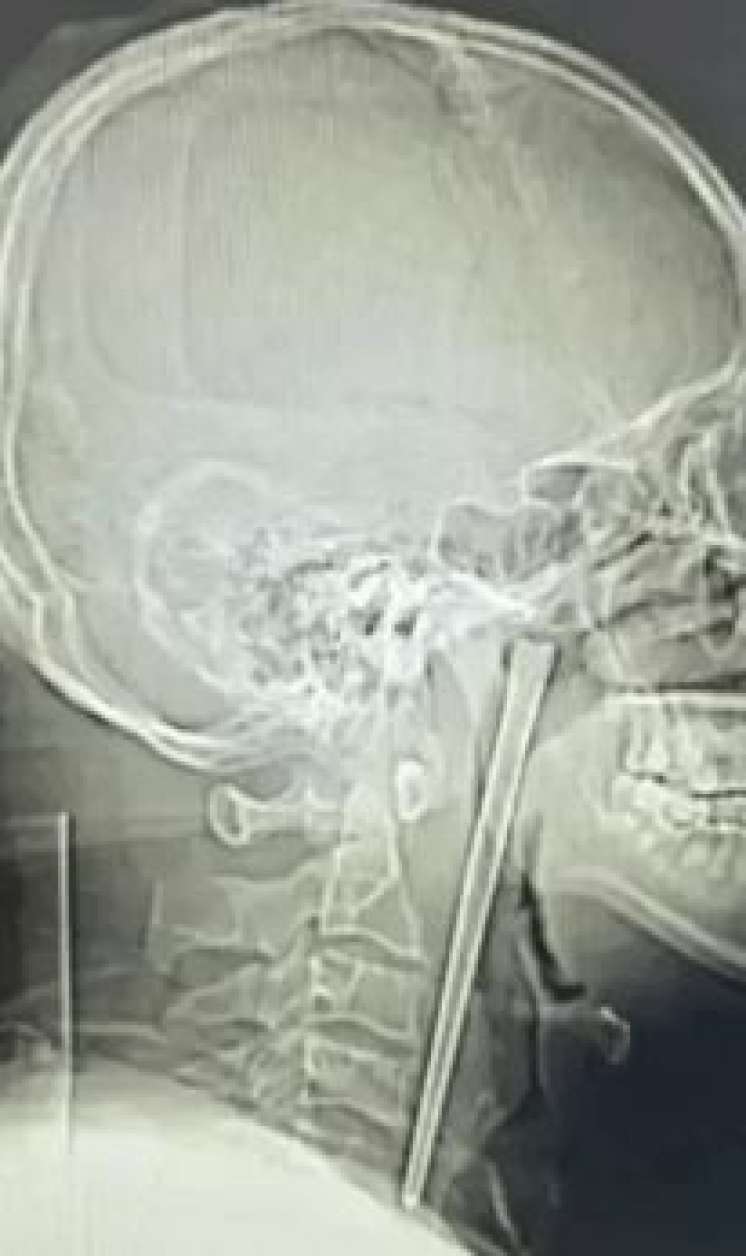

Həkimlər